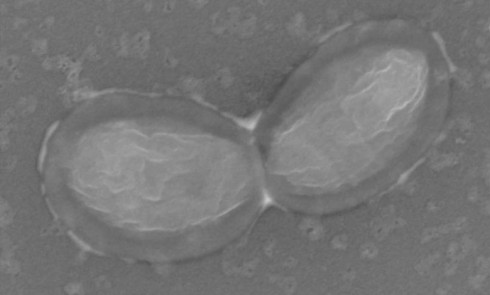

Article réservé à nos abonnés Sous la lumière bleue, les secrets de la photopolymérisation

Les techniques et les matériaux de restauration ont considérablement évolué au cours des dernières décennies. Parmi eux, les restaurations composites...